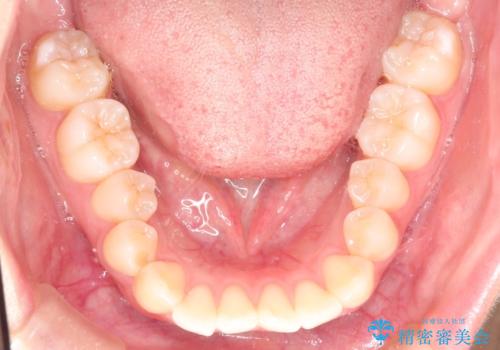

前歯のがたつきをインビザラインで目立たない矯正

- 上下の前歯のがたつきを主訴に来院されました。

マウスピースでの矯正を希望されたので、インビザラインで矯正治療を行うこととしました。

インビザラインではシュミレーションによりどのように歯が動くかを確認して矯正することができるので、患者様も安心して矯正をすることができました。